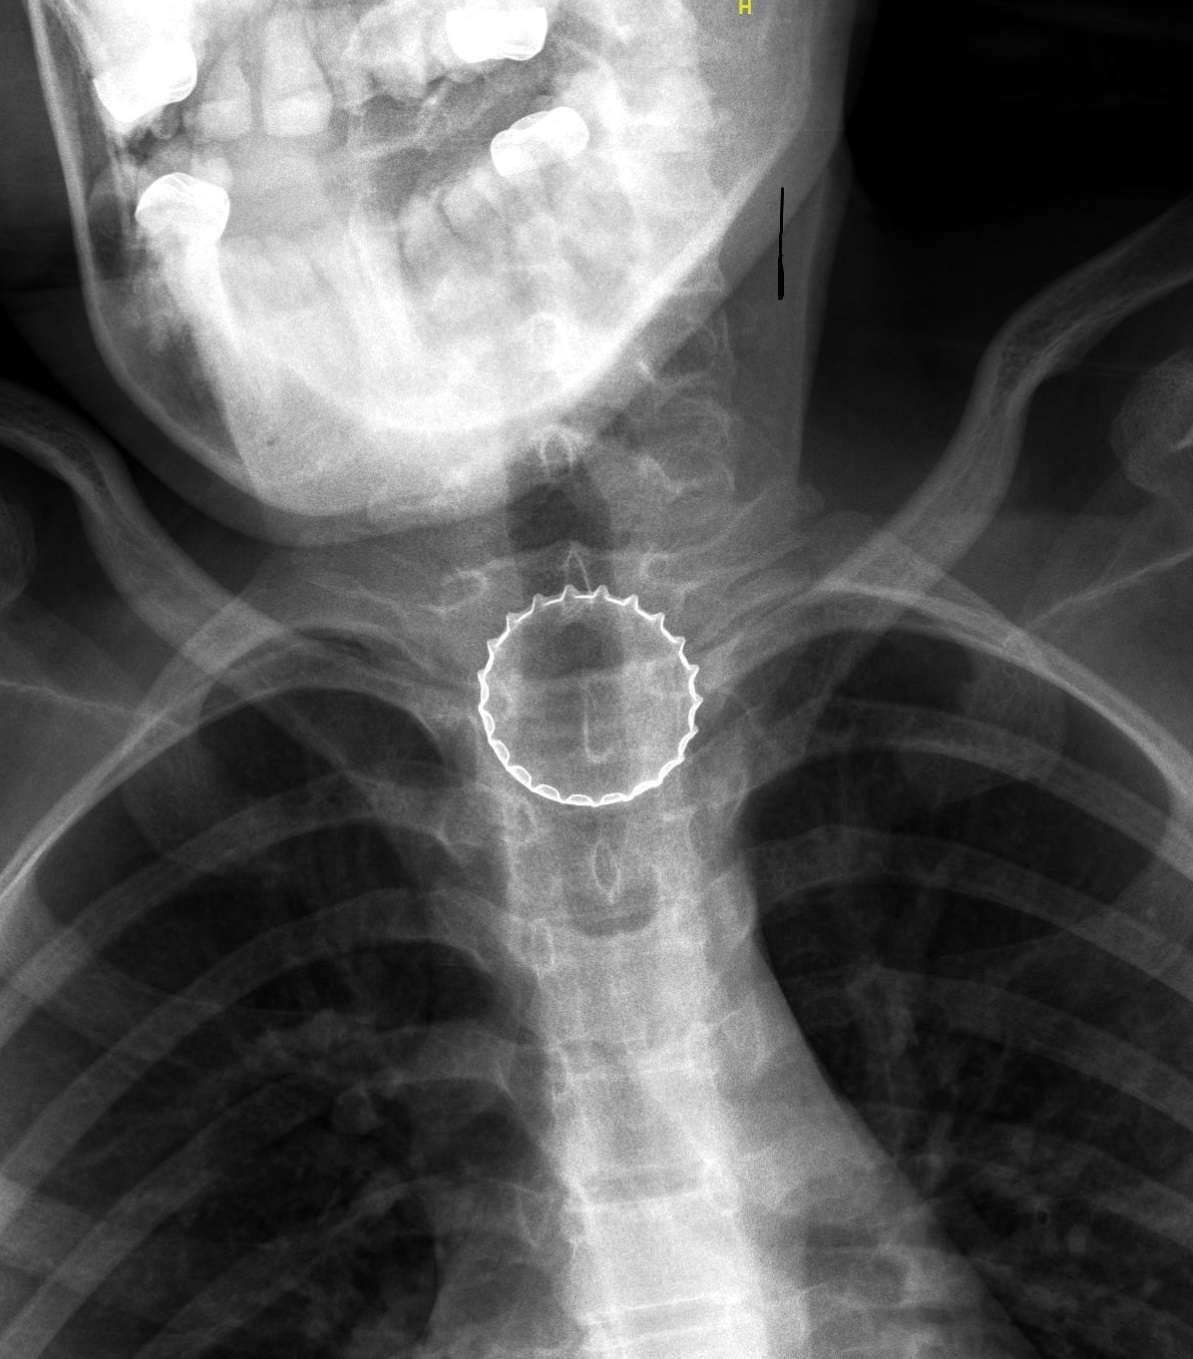

במיון ילדים עברה הנערה בירור מקיף ויסודי ע”י הצוות בראשות ד”ר עלי ח’טיב, מומחה ברפואת ילדים, ובין השאר בוצע לה צילום רנטגן, בו התגלה גוף זר בוושט. הנערה הוכנסה לחדר ניתוח, שם באמצעות ציוד אנדוסקופי ייעודי, הוצא מצינור הוושט פקק של בירה קורונה, ע”י צוות ממחלקת אף אוזן גרון וניתוחי ראש-צוואר, בניהולו של ד”ר אייל סלע. הנערה אושפזה להשגחה למשך יממה ושוחררה במצב טוב.

ד״ר איזנבך עם הפקק שהוצא בניתוח באמצעות הציוד האנדוסקופי. צילום: רוני אלברט